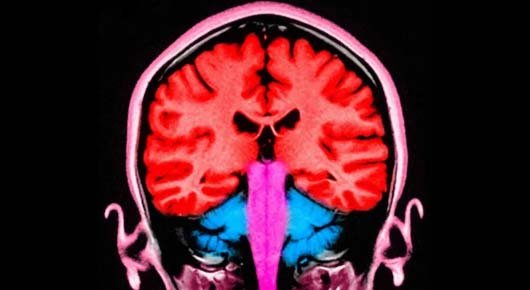

During the experiment, an electrical current was applied to the frontal and parietal areas of the brain – situated at the front and towards the back. When these areas were stimulated at the same time, the participants gave away more money.

In that study, the researchers pinpointed the two brain areas that appeared to be “talking to each other” – with brain cells firing at the same frequency – when players gave away more money.

Those two brain areas are known to play a role in decision-making and in empathy, or distinguishing the feelings of others from our own.

When a more selfless decision was made, the empathy region and the decision region appeared to communicate.